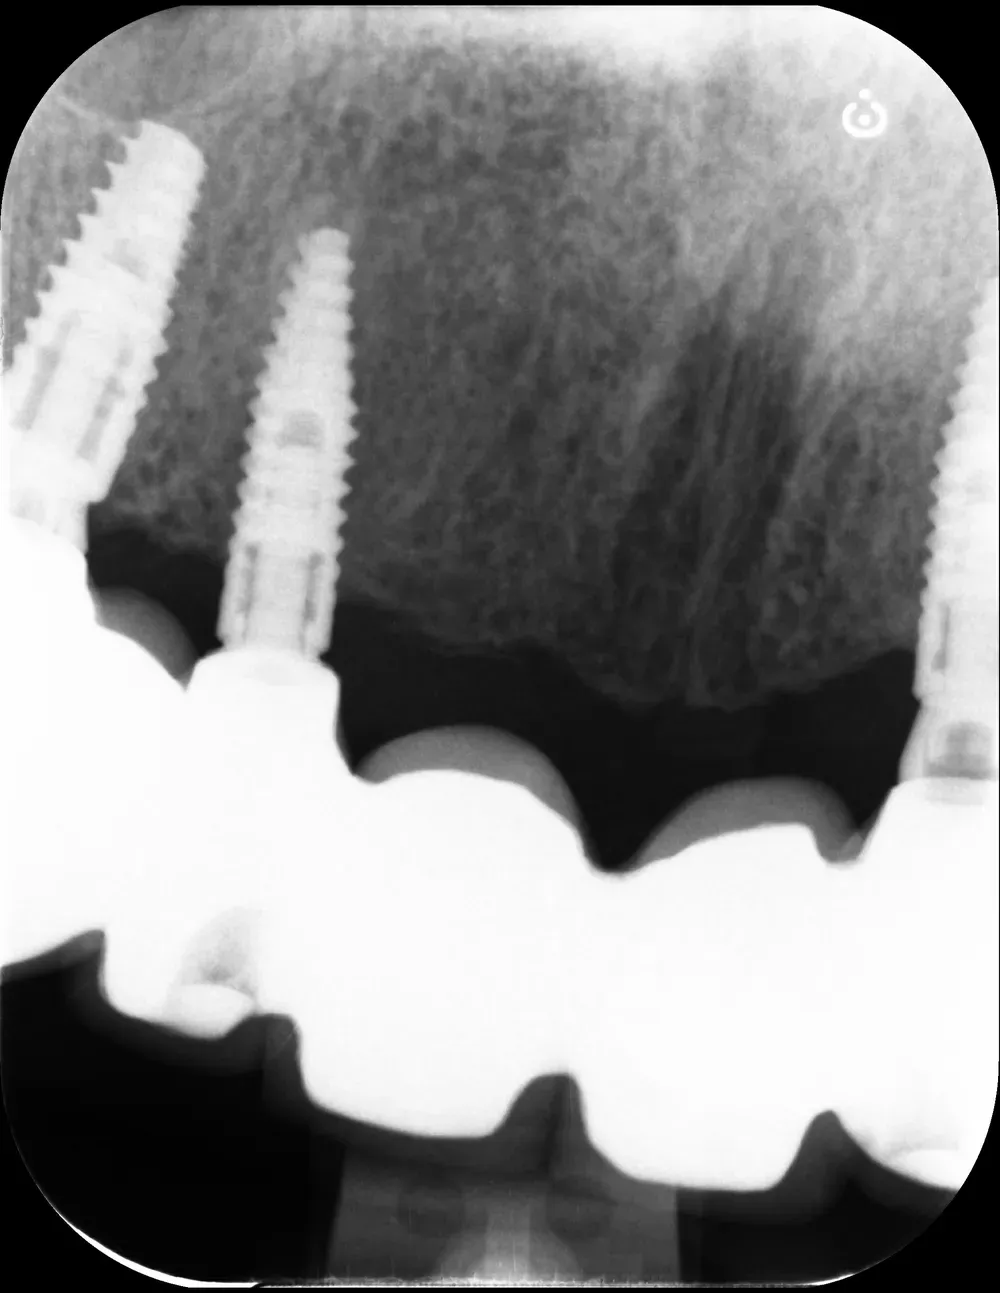

Al controllo radiografico, sette anni più tardi, gli impianti sono in ottima salute e perfettamente integrati (vedi immagini seguenti).

Francesco viene regolarmente ai controlli, in particolare per le sedute di igiene professionale.